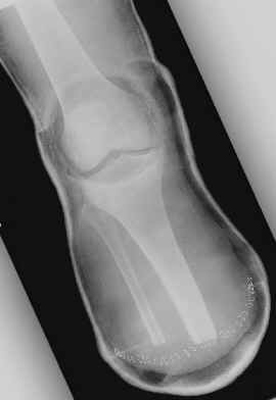

The images shown demonstrates a BKA of acceptable length. The patient is

wearing a prosthesis.